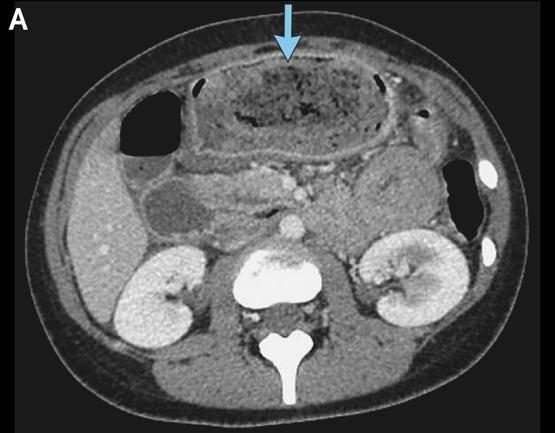

网红神药减重36斤,胃里却长“石头”:那些急功近利的减肥,都在偷偷还债 “7天瘦10斤”“不用节食运动”,当网红直播间喊出这些口号时,63岁的阿姨怎么也没想到,让自己从93公斤瘦到75公斤的“神药”司美格鲁肽,会在她胃里结出坚硬的结石。持续一个月的恶心呕吐、烧灼样腹痛,直到胃镜下那块顽固的胃石出现,才揭开了“快速减重”背后的健康陷阱。 这不是个例。江苏无锡的王阿姨把山楂当减肥神药狂炫,结果胃肠里长满大小结石,只能手术取出;北京李女士跟风买的网红“小粉片”,吃后腹泻呕吐不止,经查竟非法添加了处方药利尿剂,成本不到1元却卖69.9元。更触目惊心的是,有些“中药减肥丸”藏着甲状腺素片,让18岁姑娘瘦20斤后患上药物性甲亢,心悸手抖、月经紊乱 。这些被网红吹成“救命稻草”的产品,本质上都是用健康换体重的骗局。 为什么明知可能有风险,还有人愿意铤而走险?说到底,是“身材焦虑”催生的急功近利。我们总想着走捷径,却忘了身体从不会说谎:司美格鲁肽这类药物虽获批准减重,但需严格遵循医嘱,擅自使用可能导致胃排空延迟形成胃石;利尿剂不过是脱水假减重,长期服用会引发电解质紊乱,甚至心脏骤停 ;而山楂、柿子中的鞣酸,过量食用也会和蛋白质结合凝结成结石。那些宣称“立竿见影”的减肥神药,要么是非法添加违禁成分,要么是利用身体代谢漏洞,短期效果背后全是看不见的伤害。 真正的健康从没有捷径。医生明确建议,只有BMI达标且合并相关并发症,才能在专业指导下考虑药物减肥,而健康饮食+规律运动才是长久之计。就像那位胃结石阿姨,停用“神药”后3个月体重反弹10公斤,血糖也随之升高,此前的减重成果终究成了泡影。 减肥的本质是自律与耐心,而非赌上健康的豪赌。当我们为了数字焦虑时,不妨想想:那些偷来的快速减重,终要以器官损伤、代谢紊乱为代价偿还。与其迷信网红神药,不如相信身体的规律。你身边有没有人踩过减肥骗局?欢迎在评论区分享经历,提醒更多人别让急功近利,毁掉本该安稳的健康。